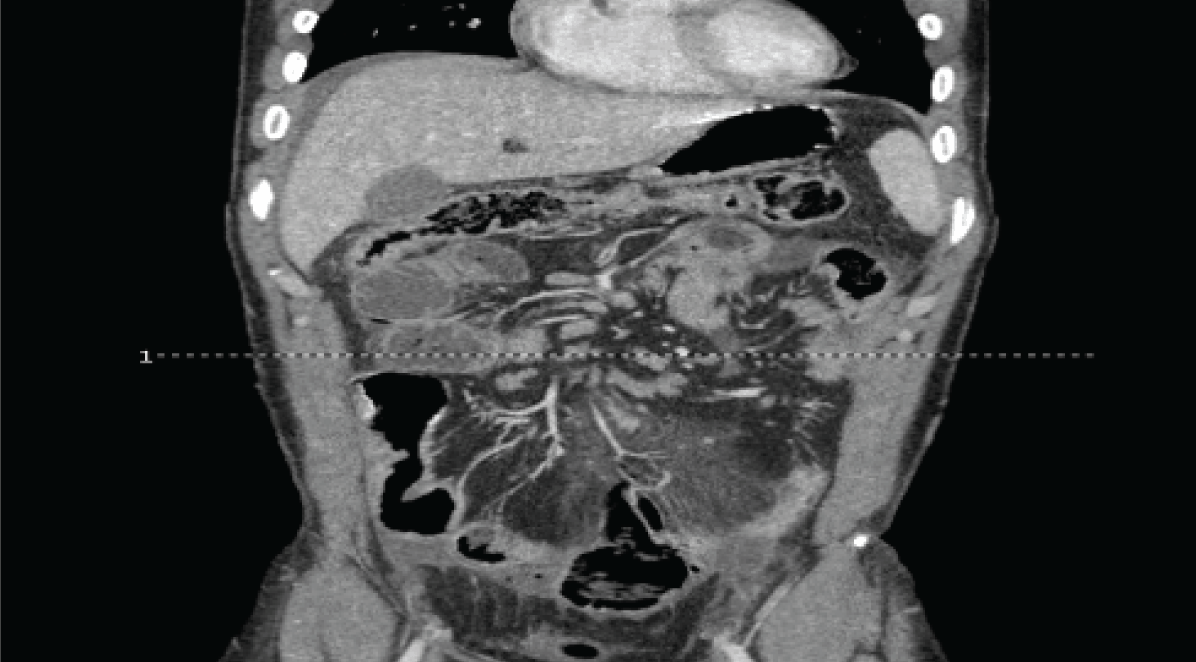

Computed tomography (CT) scan of abdomen and pelvis revealed lower abdomen bowel rupture with associated mesenteric inflammation, fecal matter, emphysema and adenopathy. (Figure 1)

It was noted that there was thickened small bowel concerning for inflammatory bowel disease. There was also mid bowel focal ileus and splenomegaly. The appendix was not visualized.

Figure 1: CT abdomen and pelvis illustrating small bowel rupture with free fluid.